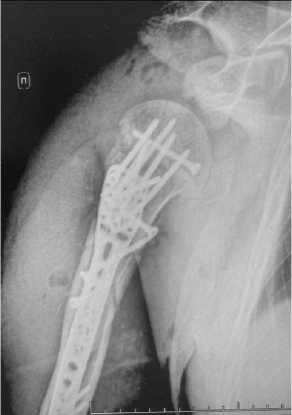

На следующий день после операции был проведён клинический анализ крови, выявлен лейкоцитоз 25×10^9/л, гемоглобин составил 120 г/л. Состояние периферический иннервации и кровоснабжения – нарушений не выявлено. Пациент получает анти-биотикотерапию в профилактической дозе цефаза-лина. Было проведено контрольное рентгенологическое исследование правой плечевой кости – удовлетворительная репозиция отломков, фиксация накостной пластиной с винтами, смещение фрагмента малого бугорка внутри (рис. 3).

Рисунок 3. Рентгенография правой плечевой кости в двух проекциях: положение отломков удовлетворительное; смещение фрагмента малого бугорка внутри

Figure 3. X-ray of the right humerus in two projections: the position of the fragments is satisfactory; displacement of the lesser tuberosity fragment is observed inward